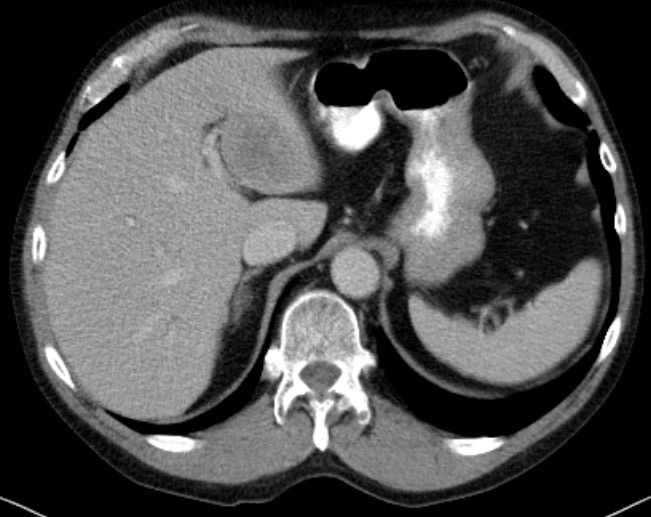

| Metastasierung | 65-jähriger Mann mit primär metastasiertem Merkelzelltumor.

Lebermetastase im linken Leberlappen![]() | ||